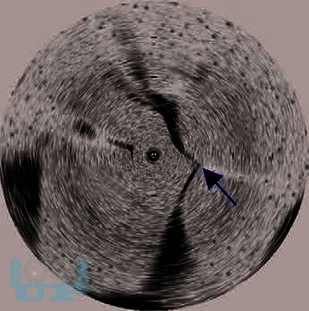

Данное издание является дополнением к знаменитому руководству Ю. Браунвальда «Болезни сердца». Большое количество иллюстраций и более 70 видео изображений позволят вам быть в курсе современных технологий и диагностических исследований, новой информации о молекулярной генетике, достижений в области аблации и многого другого. В книге подробно описаны новейшие методы диагностики и лечения пациентов с аритмией, типы аритмии описаны единообразно для быстрого ознакомления. Приведены клинические наблюдения, в частности наследственных каналопатий, фибрилляции предсердий, желудочковой тахикардии, гипертрофической кардиомиопатии, аритмогенной кардиомиопатии и врожденных пороков сердца. Клинические методы ведения сложных пациентов основаны на принципах фундаментальной науки. Видеоизображения иллюстрируют основные методы картирования, рентгенограммы демонстрируют позиционирование электрофизиологического катетера, пункции межпредсердной перегородки и доступа к перикарду, криоаблации и процедур изоляции ушка левого предсердия.